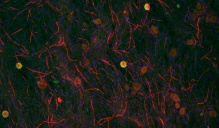

This image shows axons in vitro 24 hours after injury. The presence of Schwann cells (nuclei in cyan) helped maintain the integrity of axons (in magenta and yellow). Image credit: Elisabetta Babetto, HJKRI

Fluorescence microscopy image of in vitro model of myelin sheath (red) formation by Schwann cells around neuronal axons (green). Cell nuclei are blue. Credit: Keit Men Wong, UB.

Cell culture containing oligodendrocytes with cortical neurons. Immature oligodendrocytes (bright yellow) interact with neurons (orange) during the first steps of the myelination process. (Credit: Pablo Paez)